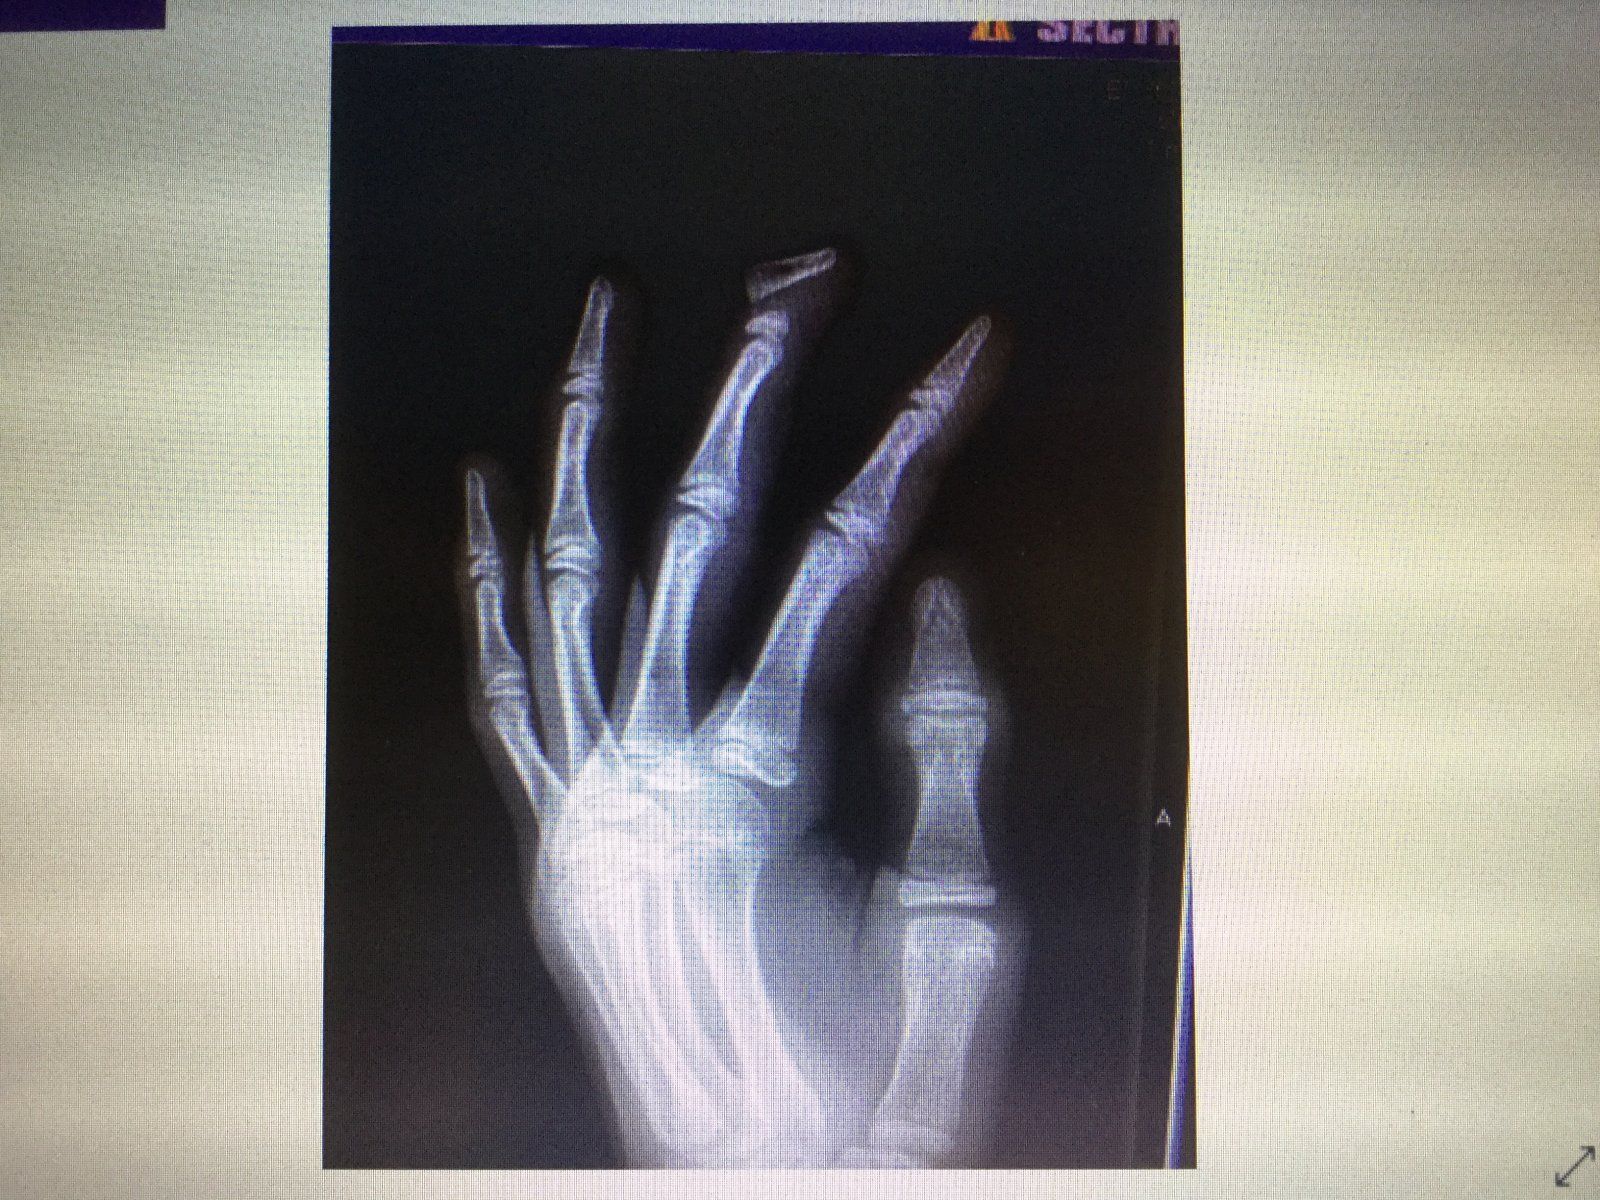

I broke my left middle finger when I was 13. Almost snapped the thing right off:

View attachment 120179

I broke it on one of those McDonald’s play places. I swung on one of the bars (with the nets strung on it) and when I did, my finger caught the net and it just snapped. I had my full body weight behind it, so I can’t really blame it.